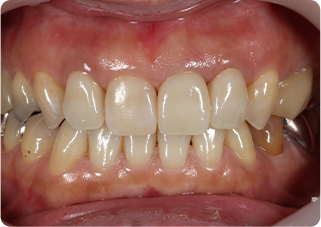

セラミッククラウン症例②

術前

仮歯

術後

| 主訴 | 前歯を綺麗にしたい、隙間が気になる |

| 治療期間/回数 | 4ヵ月、6回 |

| 価格(税込) | 792,000円(税込) |

| リスク・副作用 | セラミック破損の可能性 |

| ポイント | 仮歯で歯ぐきの状態を整え、自然な色、形となるようにオーダーメイドでセラミックを盛り、クラウンを作製した。 |